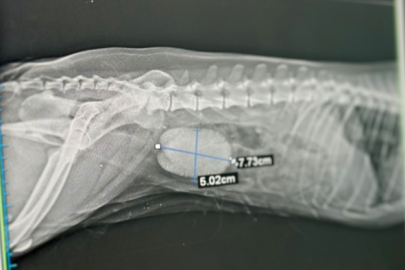

Diyarbakır’da 10 yaşındaki köpeği Fındık’ın sancılı ve kanlı idrar yaptığını fark eden sahibi, köpeğini hayvan hastanesine götürdü. Röntgeni çekilen Fındık’ın idrar kesesinde, eni 8, boyu 5 santim olan iri taş olduğu belirlendi. Fındık’ın idrar kesesini dolduran taş, operasyon sonucu çıkartıldı. Operasyon hakkında bilgi veren Dicle Üniversitesi Veteriner Fakültesi Cerrahi Anabilim Dalı Öğretim Üyesi ve Hayvan Hastanesi Başhekimi Prof. Dr. Sadık Yayla, bu boyutta bir taşa nadiren karşılaştıklarını söyledi.

Taşın neredeyse kesenin tamamını doldurduğunu belirten Prof. Dr. Yayla, “Ameliyat için hastanemize gelen fındık isimli köpeğin idrar kesesinde taşı vardı. İdrar kesesinde taş olduğu bulgularıyla zaman zaman karşılaşıyoruz ama bu boyutta taş nadir karşılaşılan bir durum. Yaklaşık 8 ve 5 santimetre ebatlarında bir taşı vardı. Hayvanın kendisi de yaklaşık 10 kilogram. Neredeyse kesenin tamamını bu taş doldurmuştu” dedi.